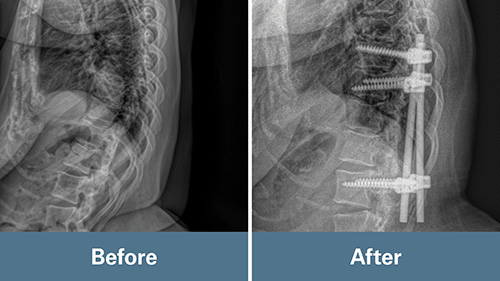

Klineberg evaluated Jaime and identified scar tissue, nerve compression, and loose implants from a previous surgery as key issues. His primary goal was to relieve pressure on Jaime’s nerves.

In December 2023, Klineberg performed a laminectomy or decompression of her lumbar and thoracic spine. He also removed the implants from her previous surgery to prevent potential problems in the future. While some surgeons stabilize the spine after decompression, Klineberg prioritizes maintaining natural spinal motion. Working through scar tissue from a previous surgery proved challenging.

“That increased the risk of further spinal cord injury,” Klineberg said. “It was a meticulous surgery because of the special anatomy and the substantial pressure.”